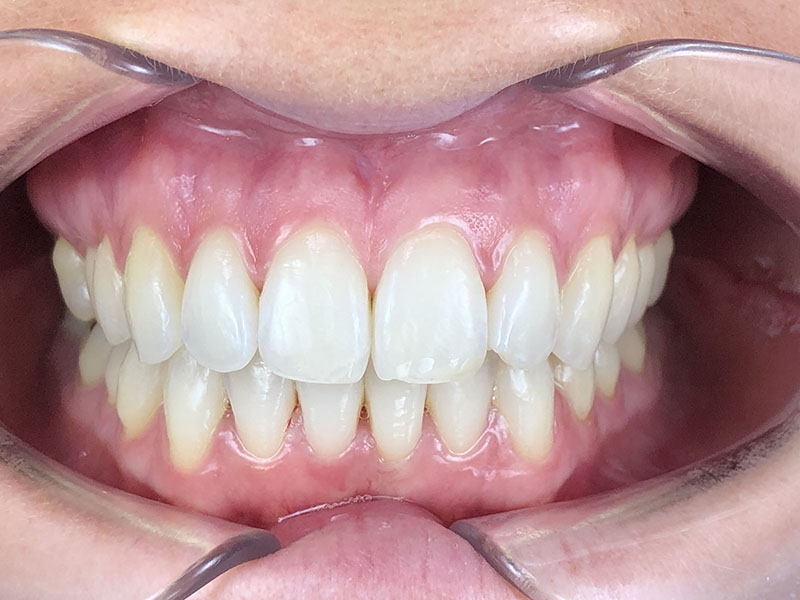

La contention finale se fera par gouttières amovibles nocturnes bimaxillaires.

Comme on peut le constater, la durée du traitement n’aura pas excédé 10 mois au final, avec deux séries de gouttières, et un stripping relativement peu invasif pour que la patiente soit satisfaite du résultat. En ajoutant un blanchiment en ambulatoire, les dents ont retrouvé un aspect éclatant.